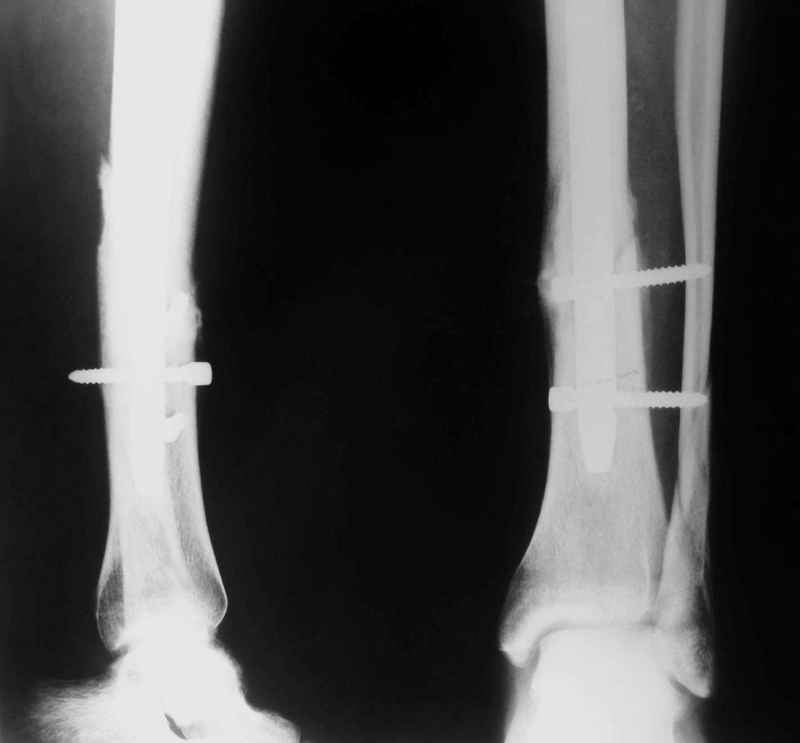

Потекли дистальные винты!

В дистальном отломке три винта( два медио-латеральных и один вентро-дорзальный).

Медио-латеральные вынты - мимо блокирующих отверстий фиксатора, вентро -

дорзальный винт - в отверстии.

Проблемы с верхним дистальным медио - латеральным винтом - он в линии перелома (

перелом косой).

То есть в дистальном отломке всего один запирающий винт. Маловато.

Если в проксимальный отломок стержень сел туго, это не мешает дистальному (широкому и короткому, раз дистальное отверстие уже на уровне перелома) быть нестабильным, особенно если он фиксирован лишь одним винтом.

Потекло через месяц - открылось 2 свища по старому рубцу от давно удаленной пластины. На фоне гноя раза три завинчивал обратно винты, которые вылезали латерально, прямо через свищ. Потом таки провел дополнительно винты мимо гвоздя, и убрал вверху статический винт. Острый гнойный процесс стих, свищи мыла она дома дважды в день водным хлоргексидином, ходила с возрастающей нагрузкой, а к 10 мес. и свищи закрылись, и срослось. Итоговые снимки от 18 апреля 2003 г. прилагаю.